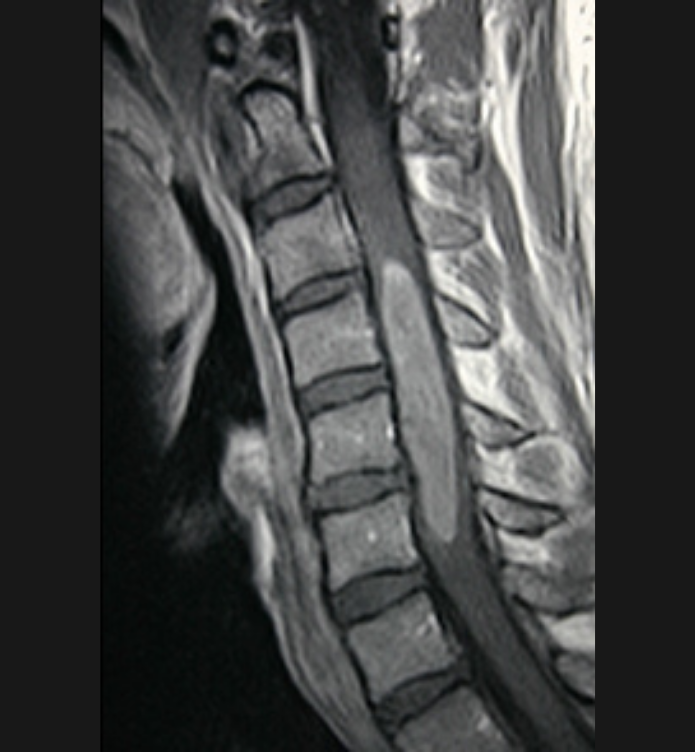

Basit Omurga ve Omurilik Anatomisi Omurga, 33 adet omur kemiğinden oluşur. Bu kemiklerin 7 tanesi boyun omuru, 12 tanesi sırt omuru, 5 tanesi bel omurudur. Beş tanesi birleşmiş olarak sakrum denilen kemiği ve 4 tanesi yine birleşmiş olarak koksiks denilen kuyruk sokumu kemiğini oluşturur. Omurganın görevi omuriliği korumak ve gövdeyi dik pozisyonda tutmak için destek […]